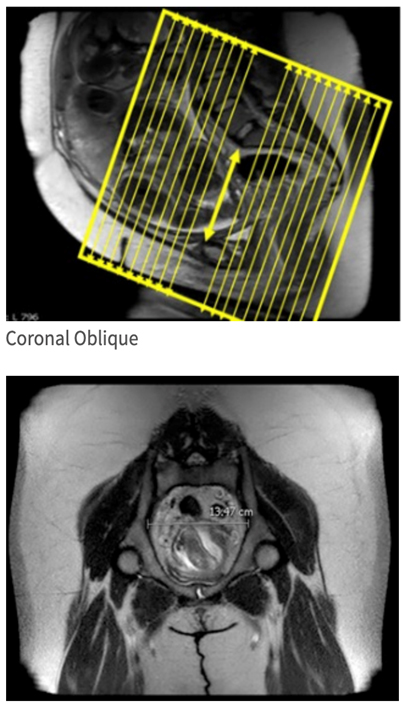

| COR OBL | T2 SS | TSE | 5mm | 1mm | None | 40cm | plane through pubic symphysis and sacral promontory |